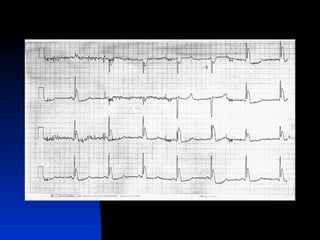

Impact on Organ

Systems

   Cardiac

   Repolarization becomes abnormal

with decreasing temperature

 Osborn   Wave – lead V3 or V4

 Increasing cardiac irritability with

decreasing temperature

 QT prolongation (0.45-0.688 vs.

0.343-0.444; Coll Antropol 1999

Dec; 23(2):683-90)

Osborn Wave

   86% of hypothermic patients (Acad

Emerg Med 1999 Nov;

6(11):1121-6)

   Voltage gradient due to action

potential notch in epicardium;

epicardium activated later, which

manifests as notching or J-point

elevation (Circulation 1996 Jan

15;93(2):372-9)